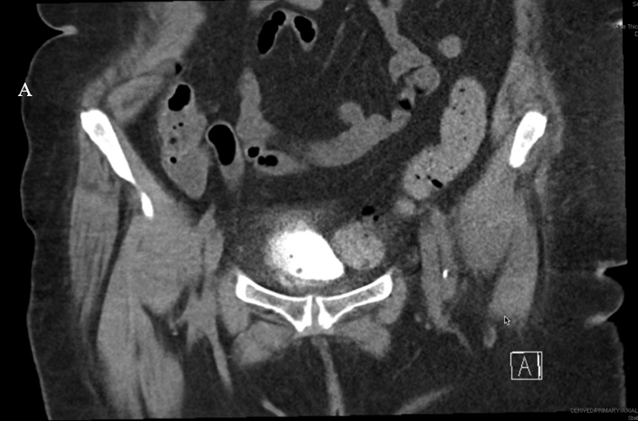

A CT cystogram was obtained at 4 weeks, which confirmed an intact bladder wall without perforation (Figure 3). The patient’s lower urinary tract symptoms were resolved upon her follow-up.

Figure 3: CT cystogram obtained at 4 weeks postoperatively demonstrating an intact bladder wall without evidence of perforation.